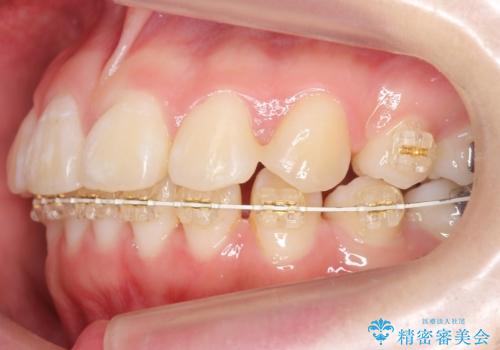

- 審美装置

成人式の1年前から矯正をはじめ、成人式前に上の前歯の装置を一時的にとりました。

一時的に装置を取ることで、多少治療期間が伸びましたが、それでも、2年かからずに外すことができました。